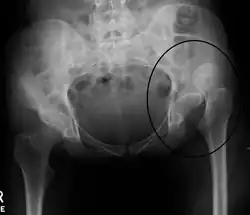

An anterior-posterior (AP) X-ray of the pelvis and a cross-table lateral X-ray[24] of the effected hip are ordered for diagnosis.[4][5][16] The size of the head of the femur is then compared across both sides of the pelvis. The affected femoral head will appear larger if the dislocation is anterior, and smaller if posterior.[7] A CT scan may also be ordered to clarify the fracture pattern.[20]